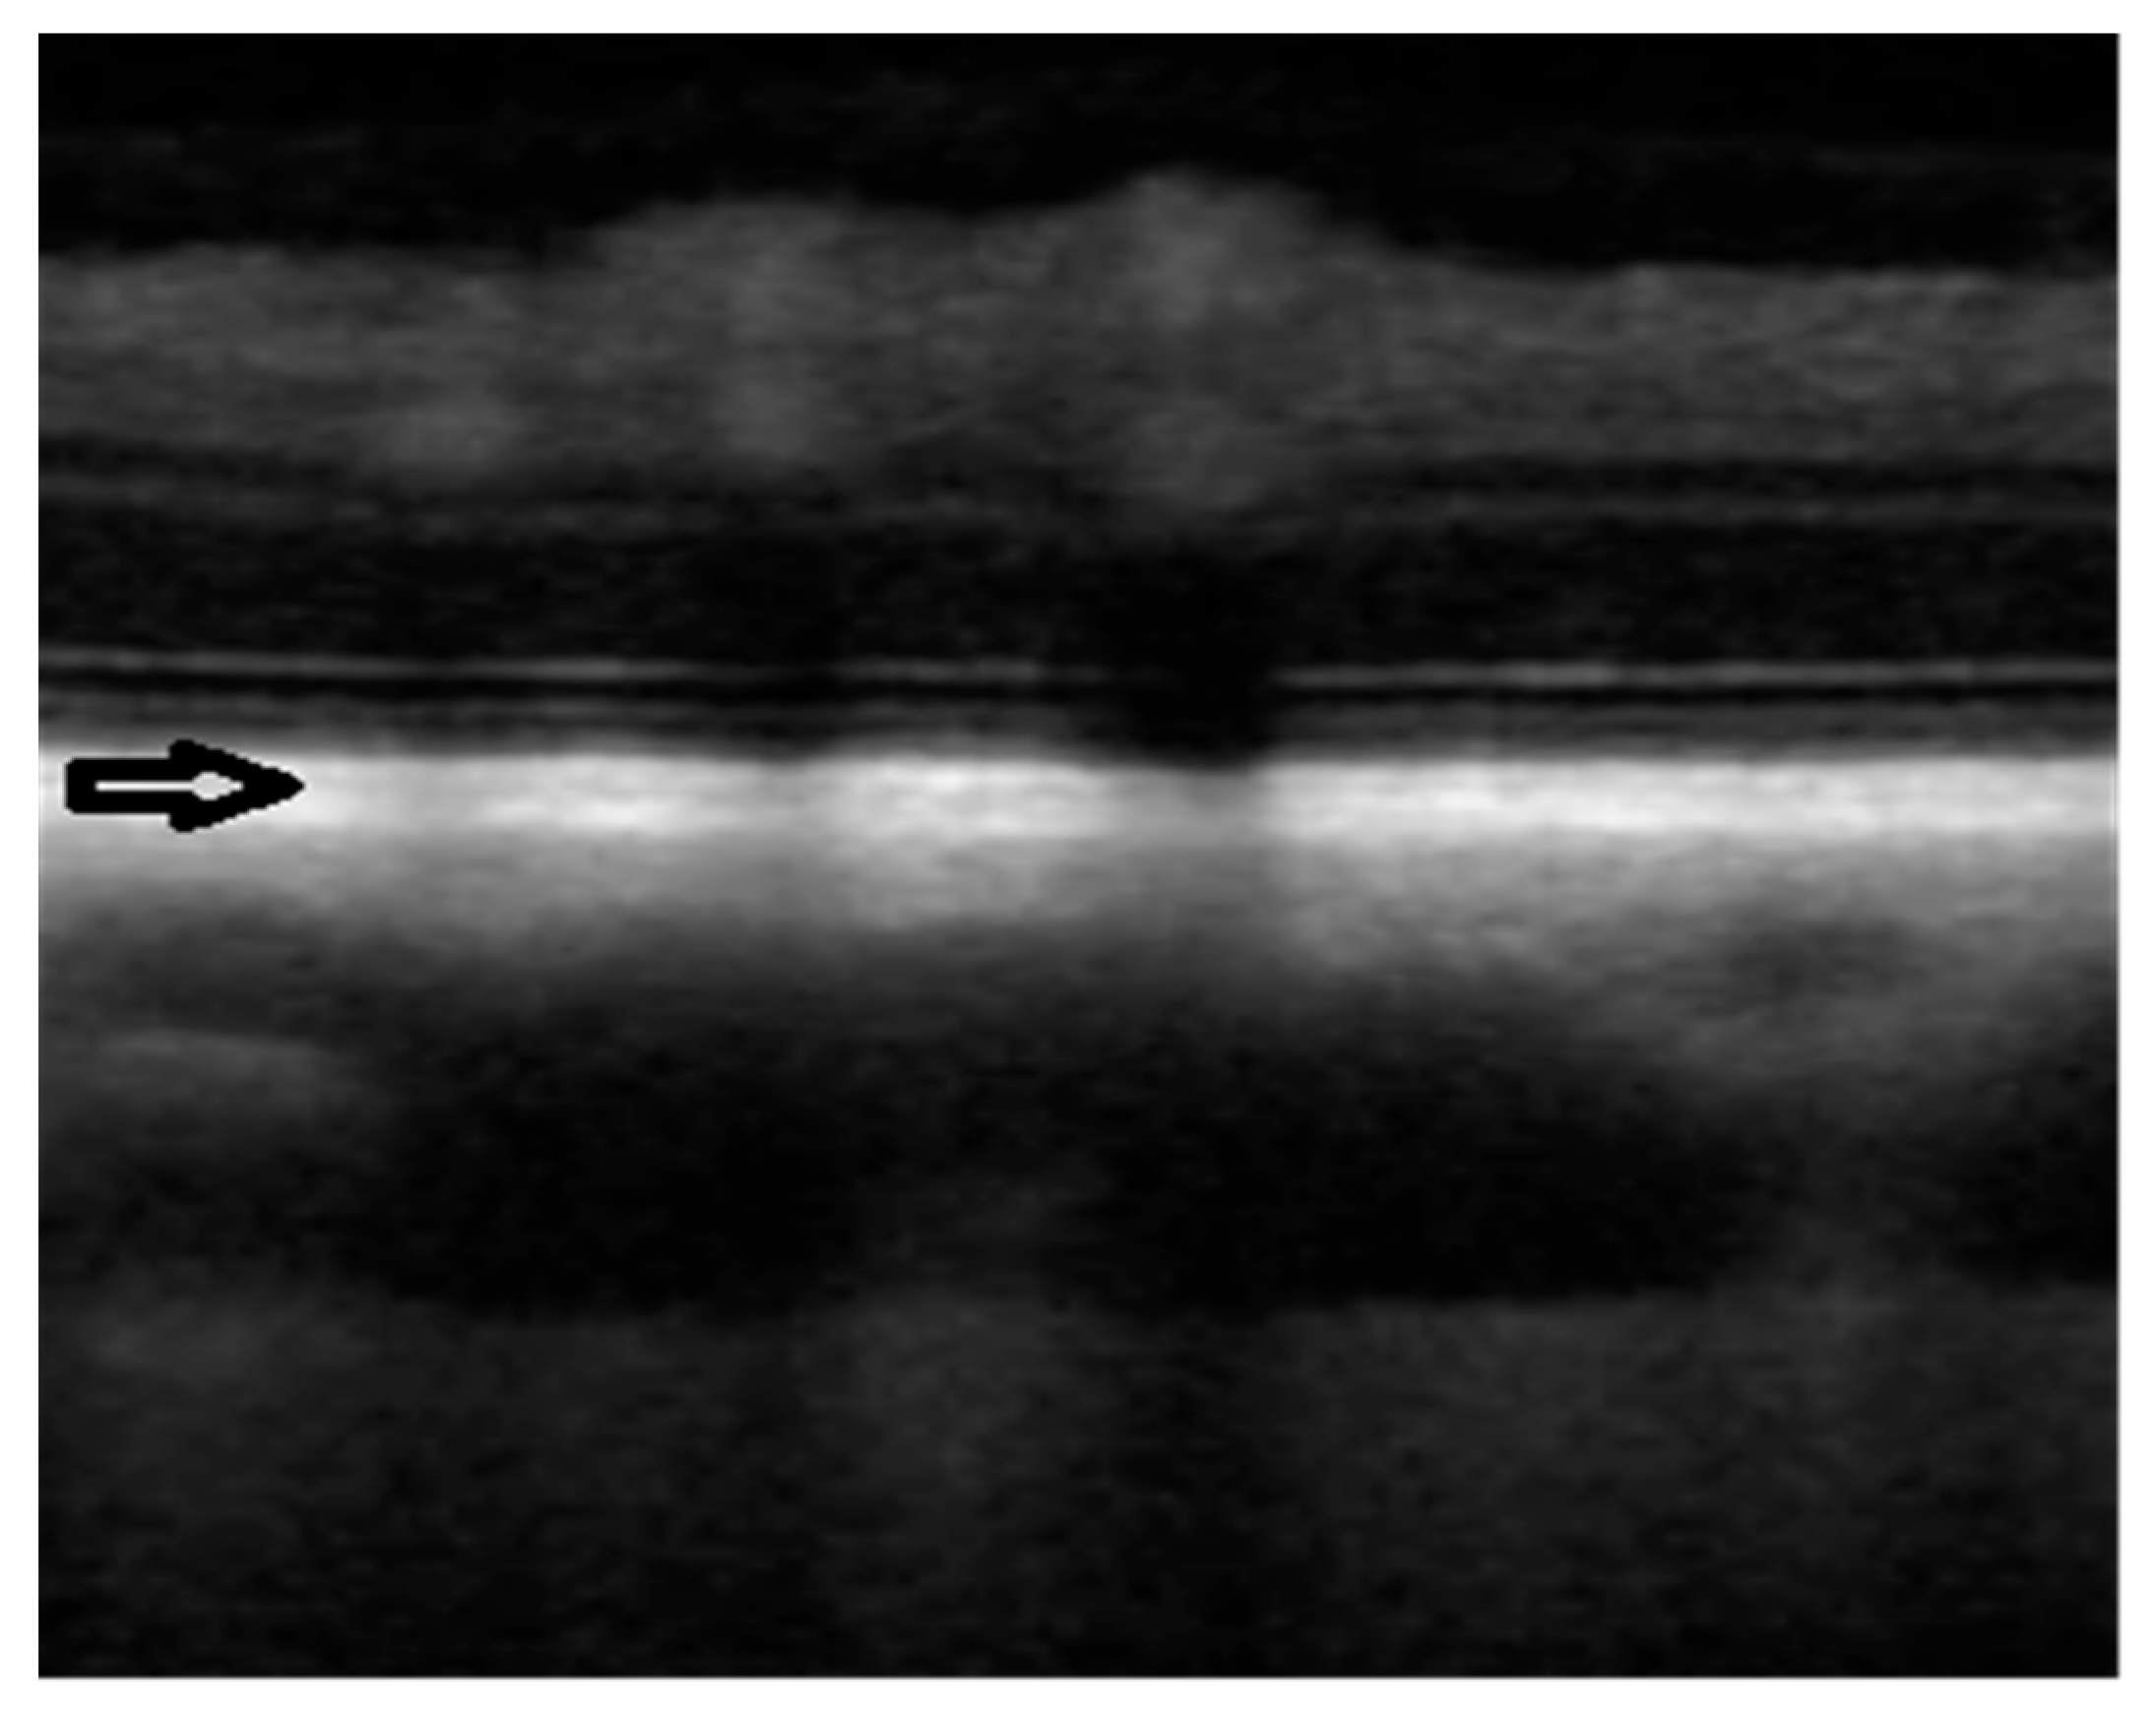

3. Results